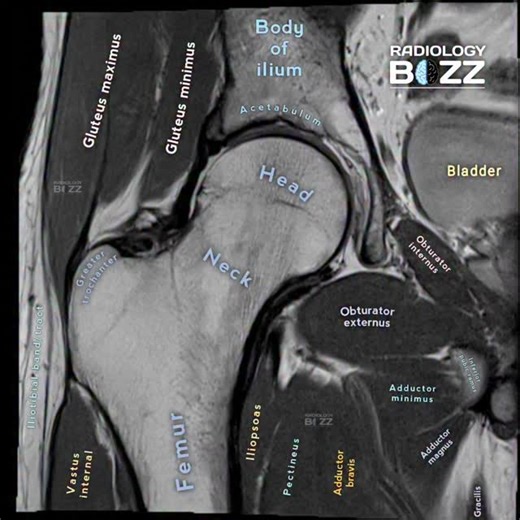

🧲MRI HIP JOINT ANATOMY – CORONAL VIEW😊 This beautifully labeled coronal MRI of the hip joint highlights the detailed anatomy of the femoral head & neck, acetabulum, body of ilium, and surrounding muscle groups including the gluteals, iliopsoas, obturator muscles, and adductors. Understanding normal MRI anatomy is the foundation for detecting pathology such as avascular necrosis, labral tears, fractures, muscle injuries, and hip impingement syndromes. 📌 Perfect reference for radiographers, rad